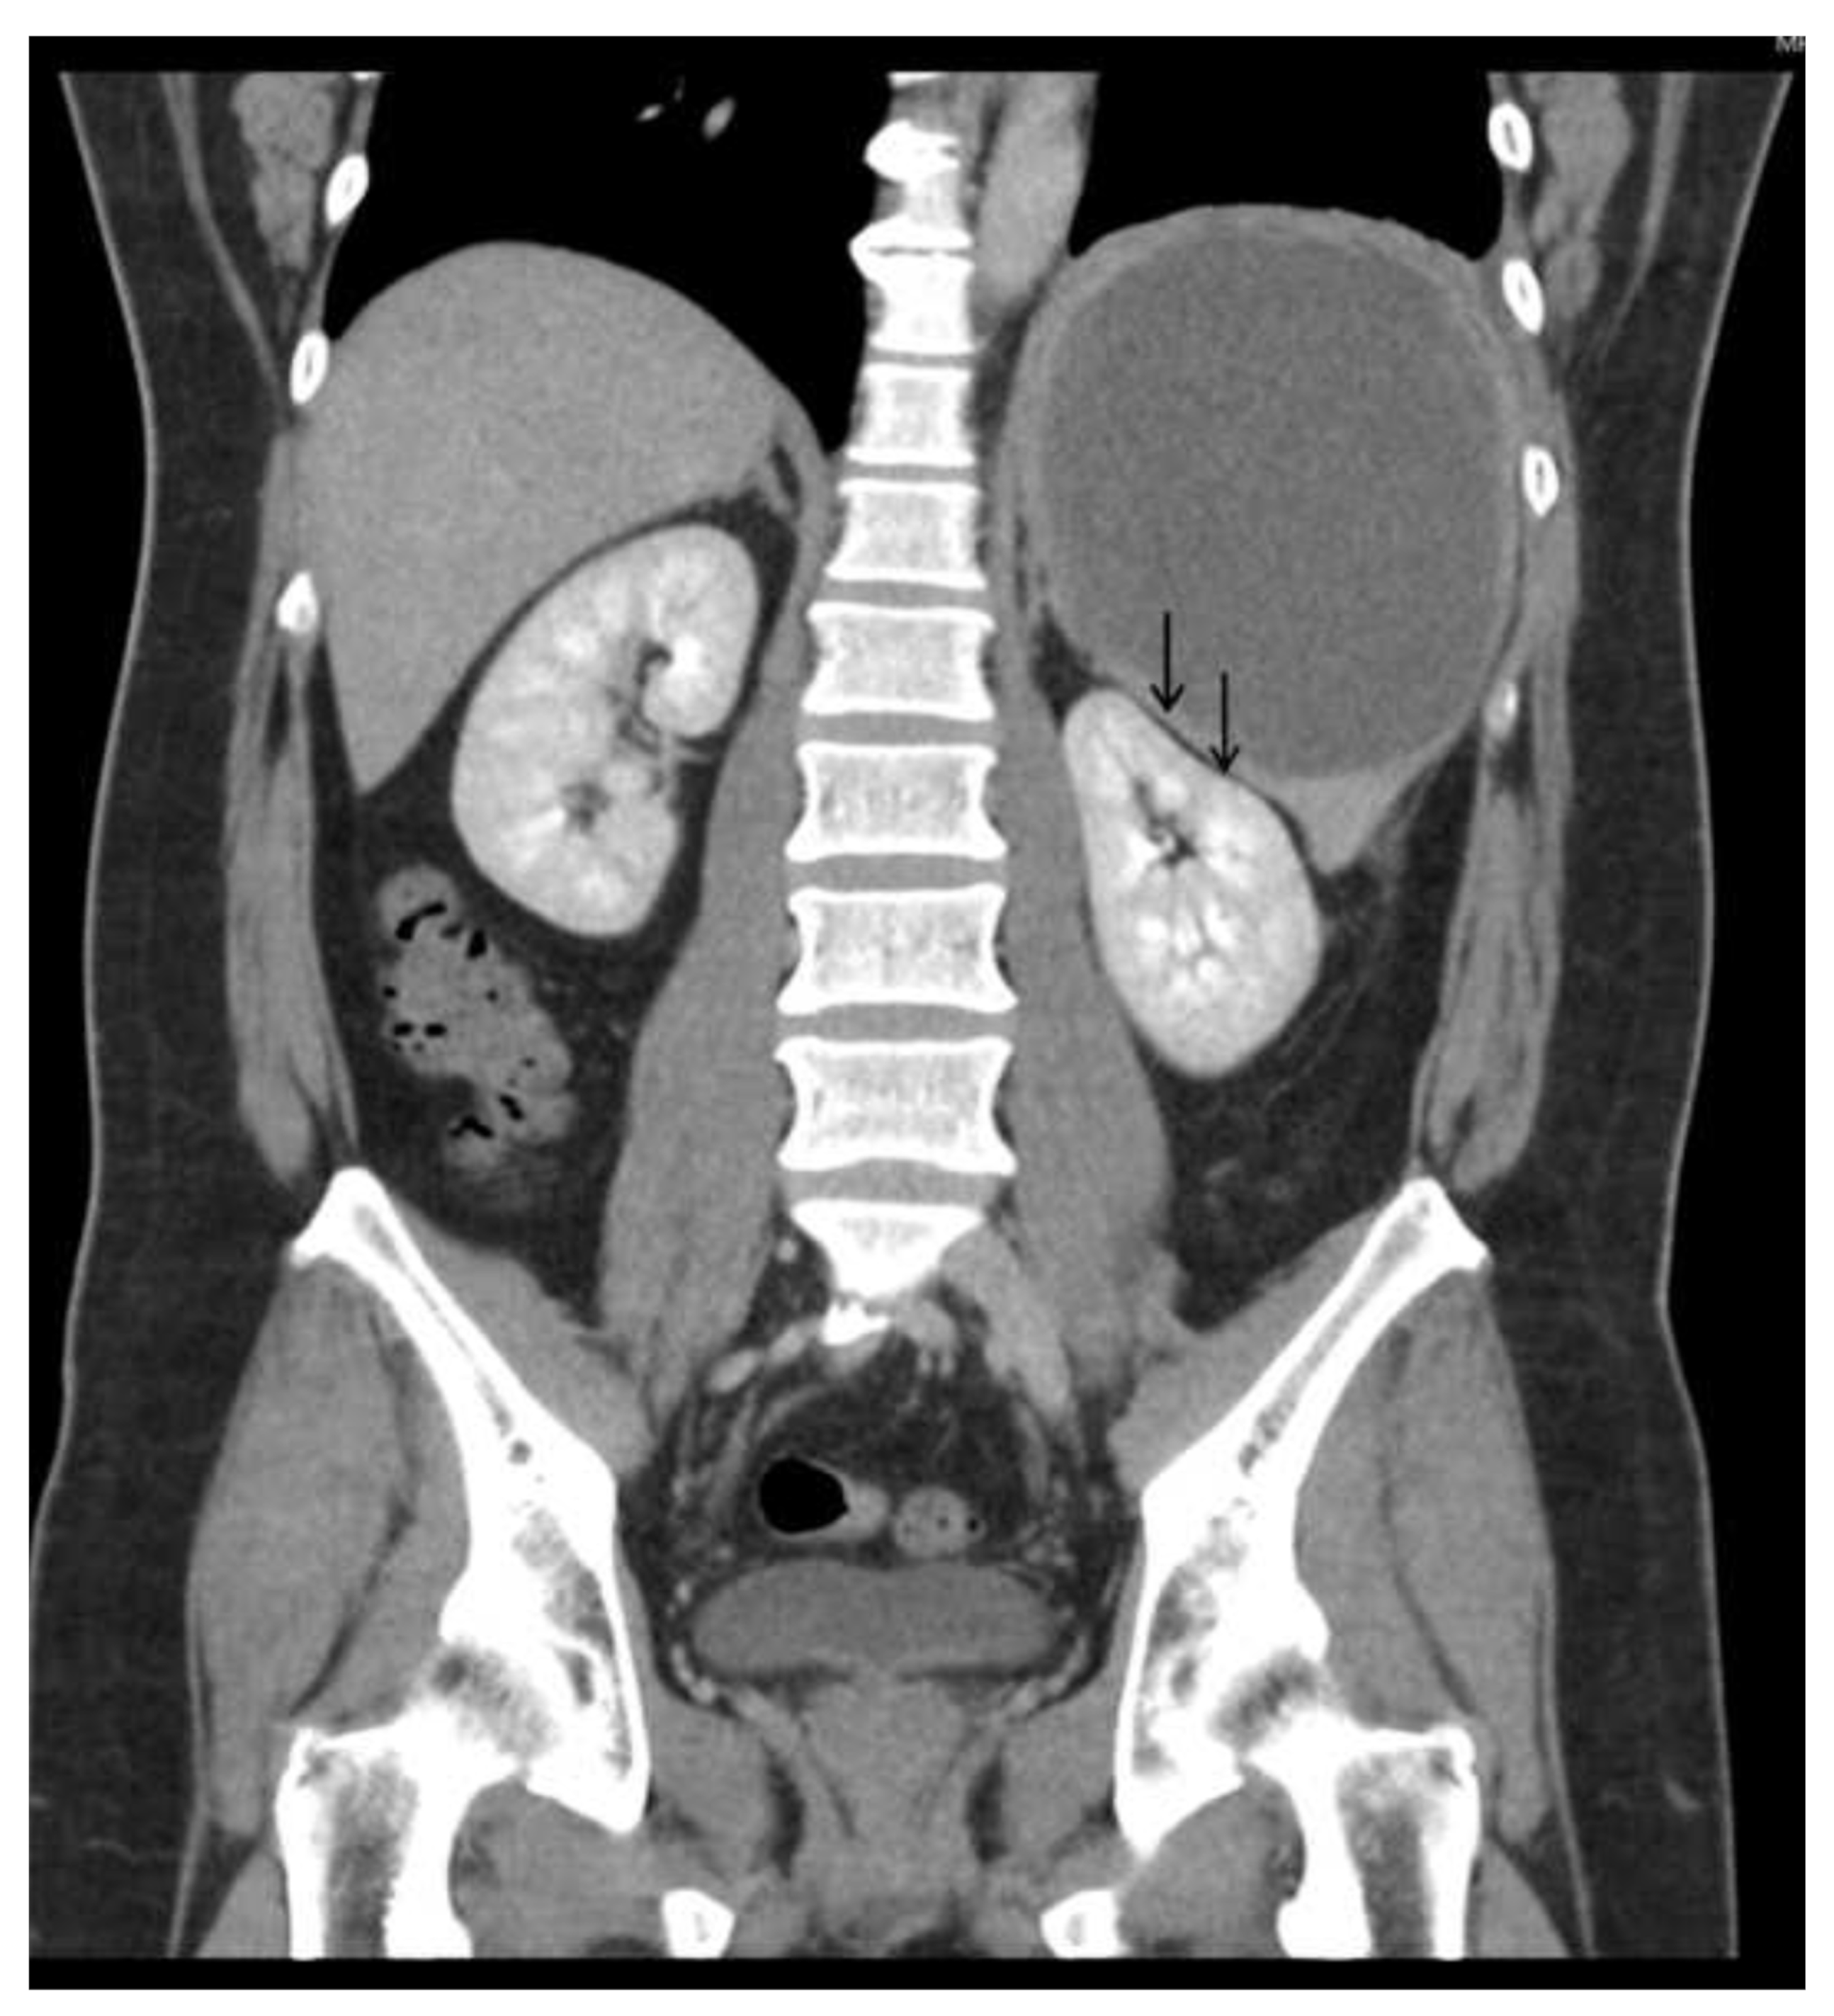

Physical examination revealed a large palpable mass with local tenderness over the LUQ. The patient’s white blood cell count was 17,000/μL, with segment neutrophil 83% and lymphocyte 10%, and platelet: 475,000/mL. An abdominal computed tomographic (CT) scan revealed a large cystic splenic mass measuring 14 cm without enhancement after contrast medium (Figure 2). The mass was pushing the left kidney inward and down (Figure 3). During the initial diagnosis, a pancreatic pseudocyst involving the spleen was suspected, and the patient received an emergency splenectomy because of the rapid growth of the mass and severe pain.

Figure 2.

Abdominal CT scan revealed a large cystic splenic mass measuring 14 cm without enhancement.

Figure 3.

Abdominal CT scan showed the mass was pushing the left kidney inward and down.